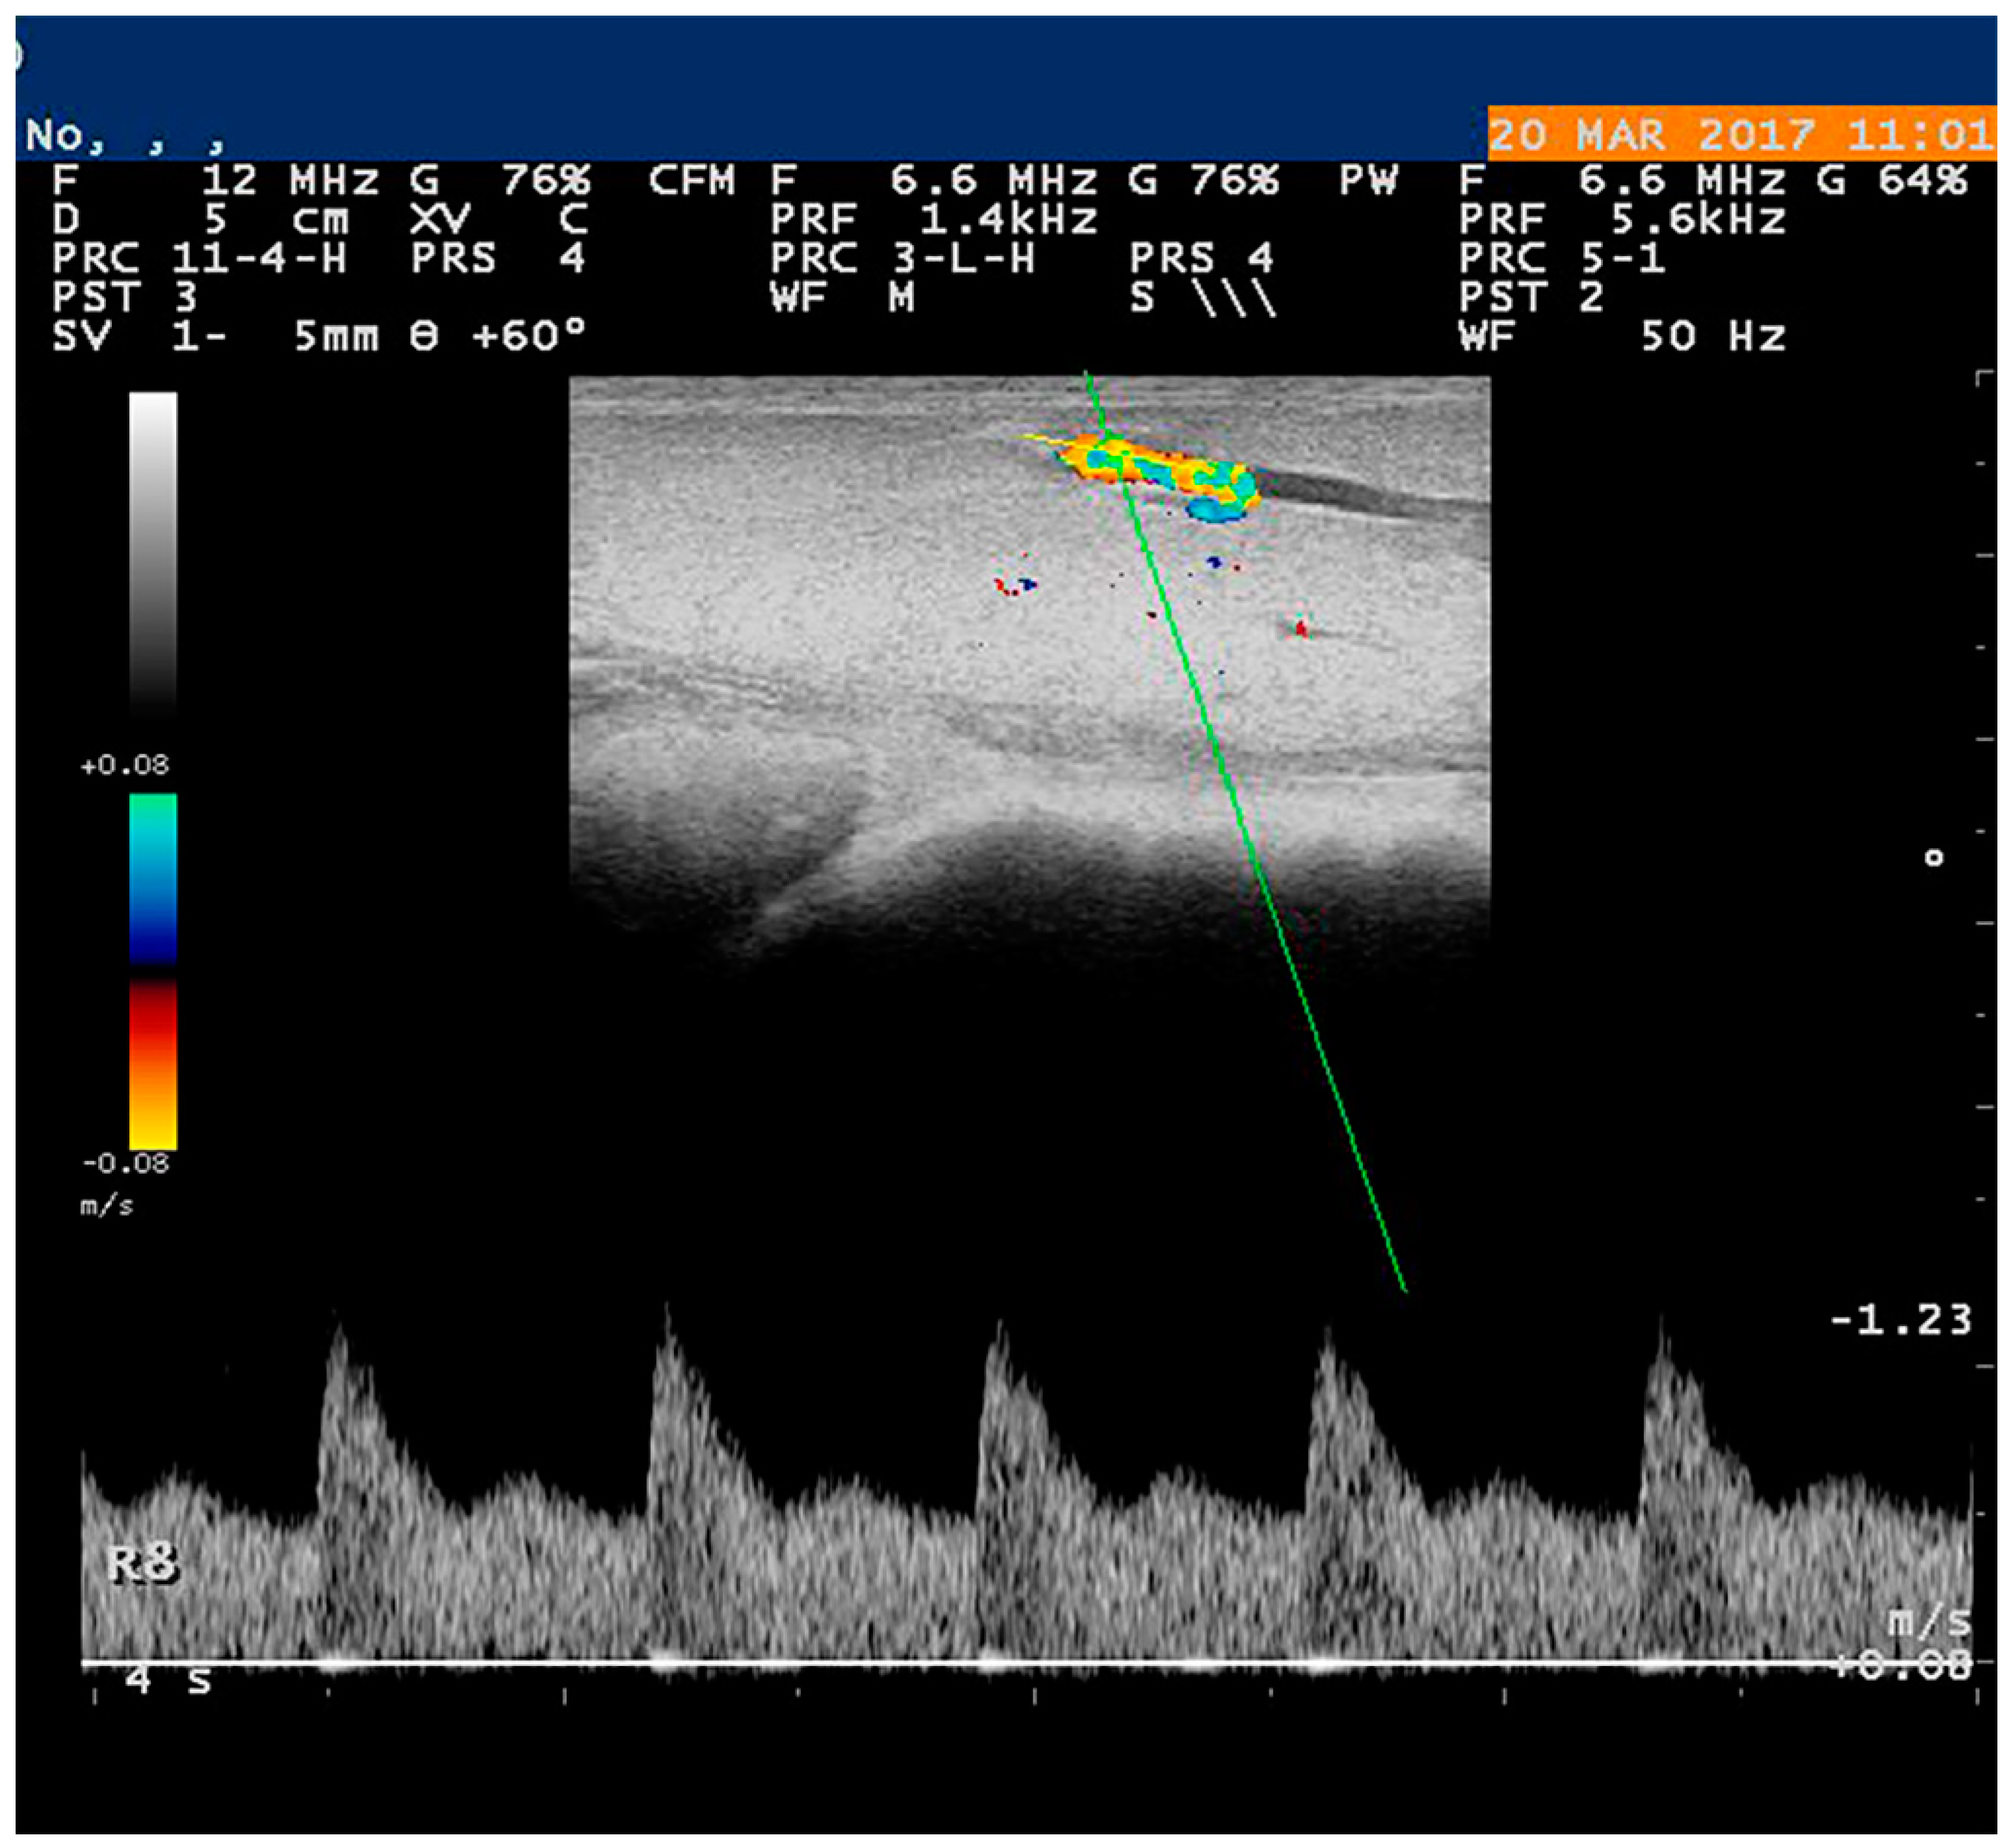

5.1. Doppler Examination

- Petridis, I.G.; Barbagianni, M.S.; Ioannidi, K.S.; Samaras, E.; Fthenakis, G.C.; Vloumidi, E.I. Doppler ultrasonographic examination in sheep. Small Rumin. Res. 2017, 152, 22–32. [Google Scholar] [CrossRef]

- Feliciano, M.A.; Vicente, W.R.; Silva, M.A. Conventional and Doppler ultrasound for the differentiation of benign and malignant canine mammary tumours. J. Small Anim. Pract. 2012, 53, 332–337. [Google Scholar] [CrossRef]

- Piccione, G.; Arcigli, A.; Fazio, F.; Giudice, E.; Caola, G. Pulsed wave-Doppler ultrasonographic evaluation of mammary blood flow speed in cows during different productive periods. Acta Sci. Vet. 2004, 32, 171–175. [Google Scholar] [CrossRef]

- Piccione, G.; Arcigli, A.; Assenza, A.; Percipalle, M.; Caola, G. Pulsed wave-Doppler ultrasonographic evaluation of the mammary blood flow in the ewe. Acta Vet. Brno 2004, 73, 23–27. [Google Scholar] [CrossRef]

- Soler, M.; Dominguez, E.; Lucas, X.; Novellas, R.; Gomes-Coelho, K.V.; Espada, Y.; Agut, A. Comparison between ultrasonographic findings of benign and malignant canine mammary gland tumours using B-mode, colour Doppler, power Doppler and spectral Doppler. Res. Vet. Sci. 2016, 107, 141–146. [Google Scholar] [CrossRef] [PubMed]